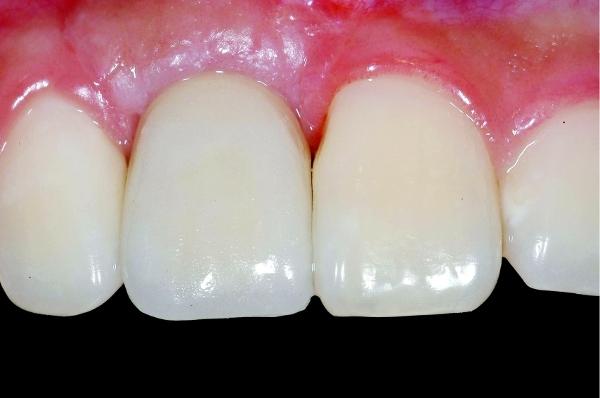

Sterowana regeneracja kości. Poszerzenie wyrostka zębodołowego żuchwy.